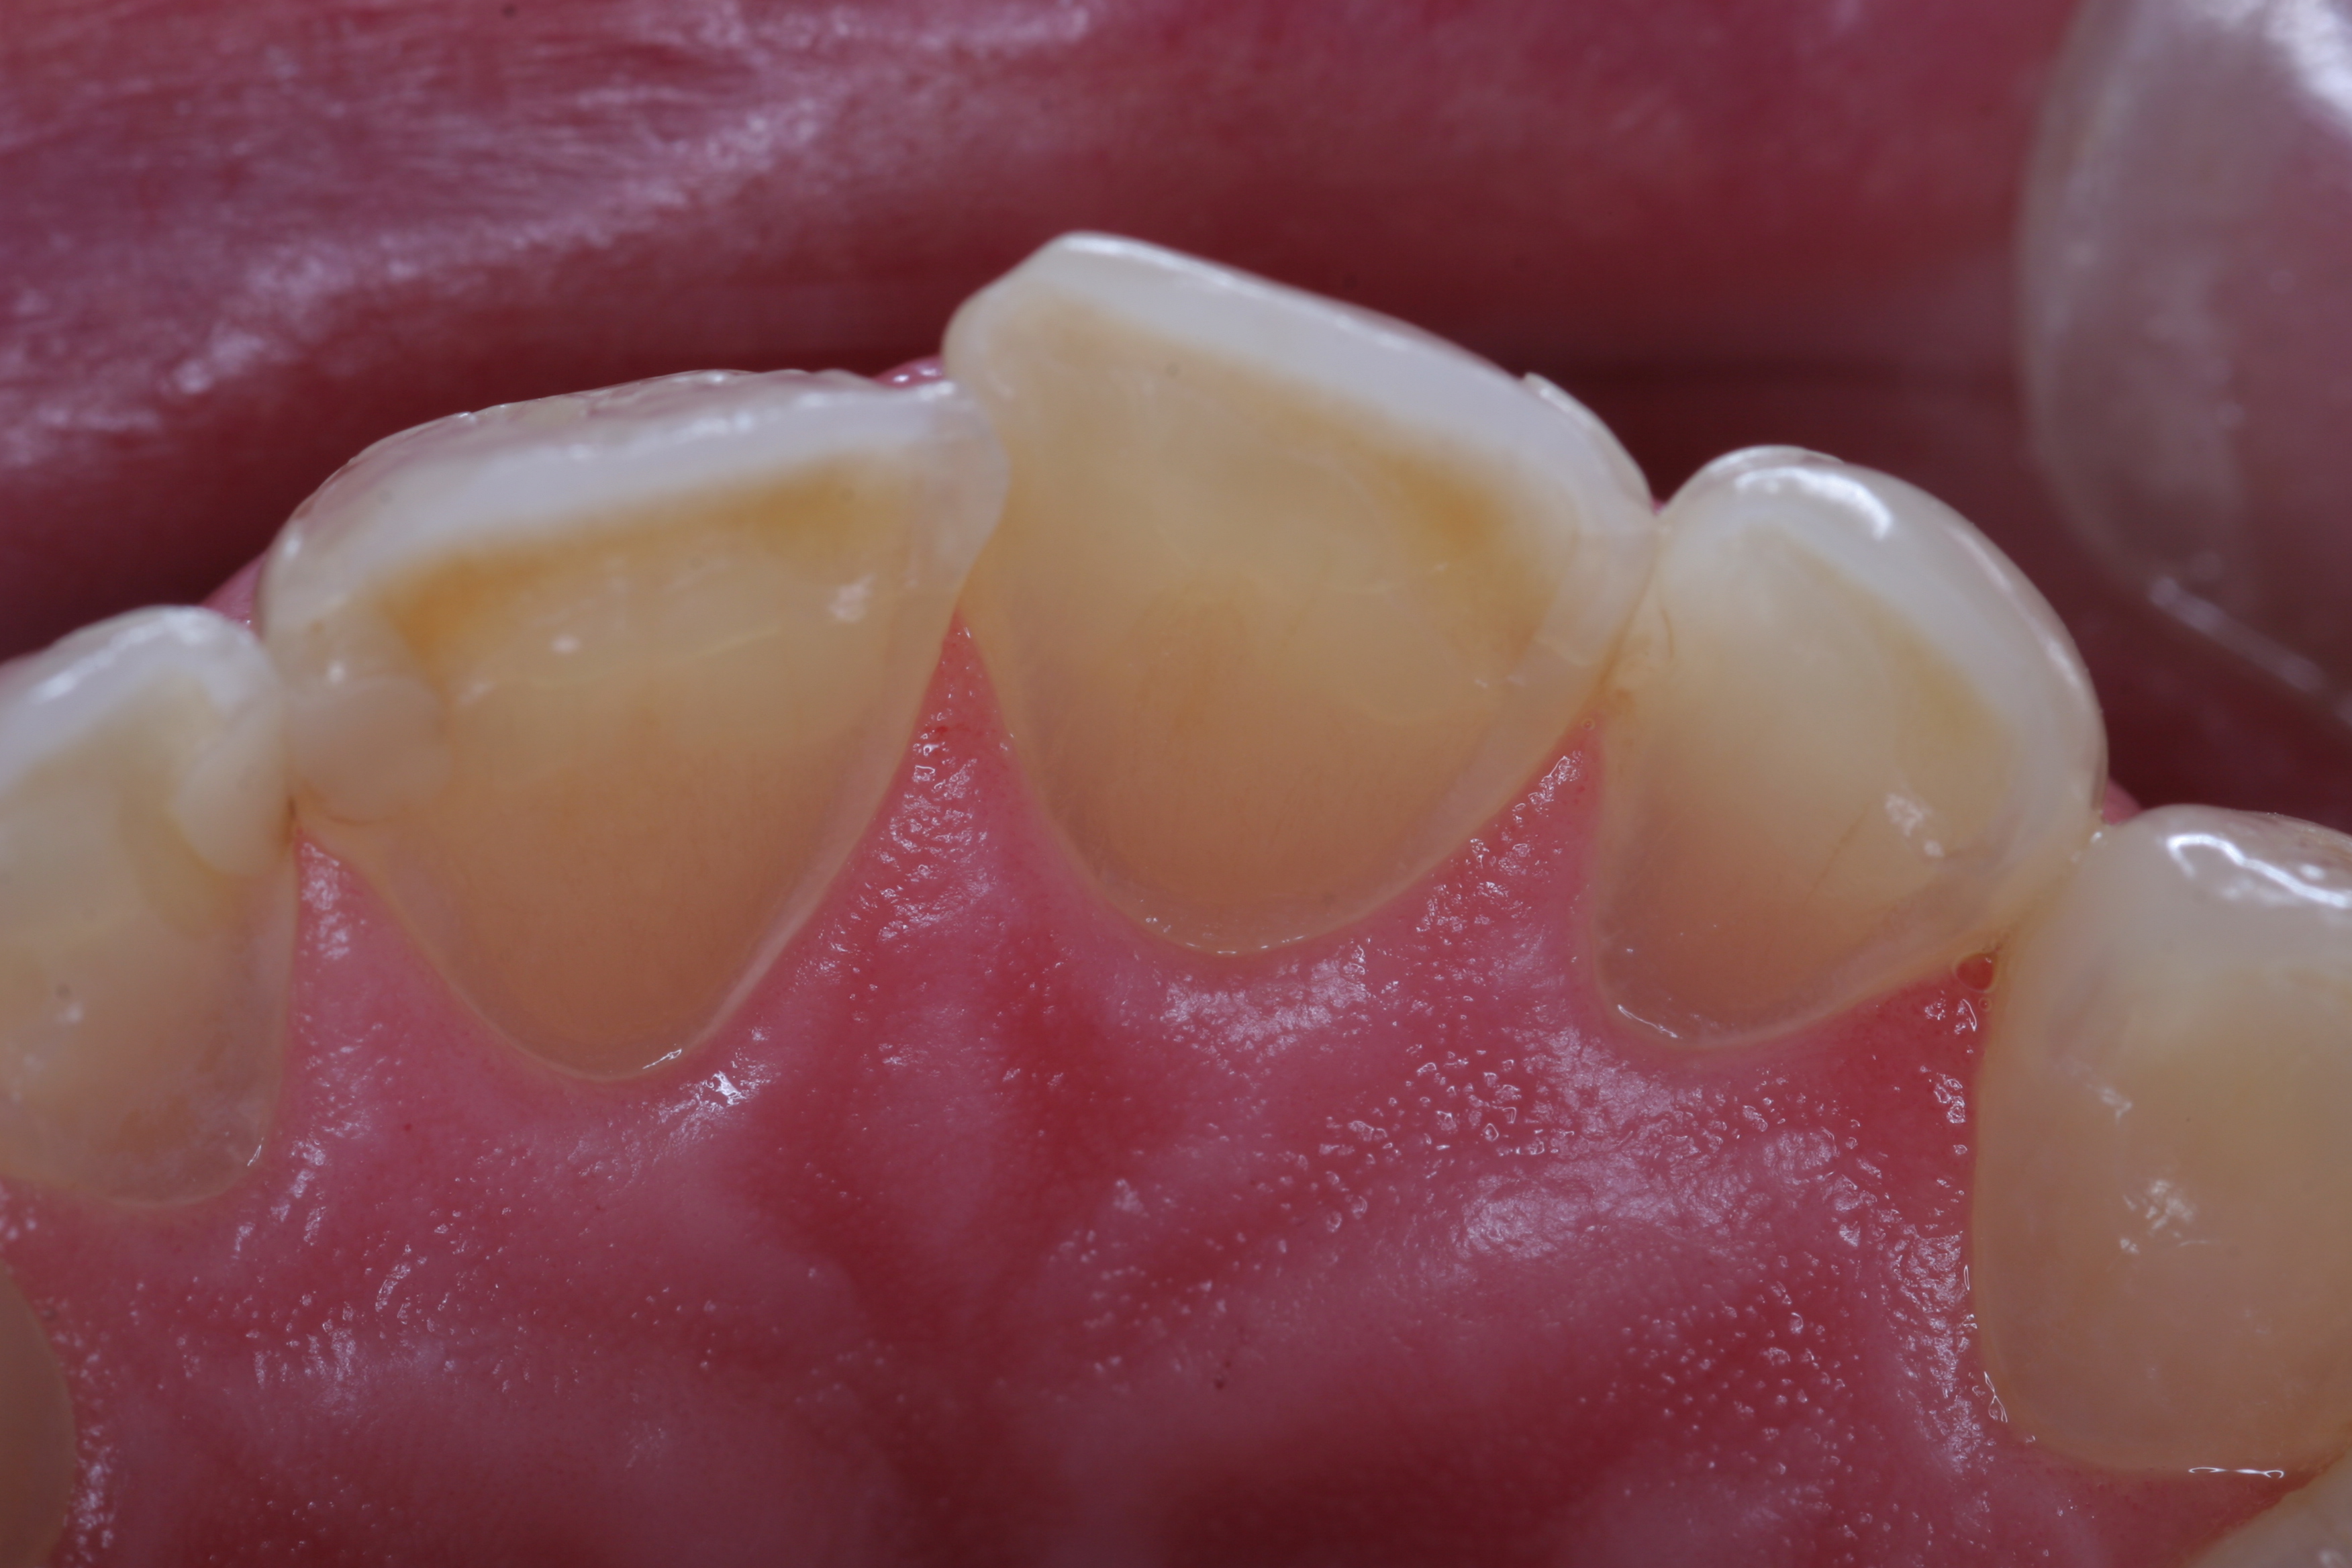

(5.) The anterior teeth must have sufficient lingual contour to allow immediate disclusion of the posterior teeth.

Figure 5

Abfraction was a term first described by John O. Grippo, DDS, in 1991. These cervical-type lesions result from concentrated stress transmitted through occlusal loading forces. With regard to lateral forces in the posterior region, loaded teeth showed a loss of enamel 10 times greater than unloaded teeth.8 Inadequate canine and protrusive guidance can also lead to excessive posterior tooth abrasion and advanced wear. The anterior teeth must have sufficient lingual contour to allow immediate disclusion of the posterior teeth (Figure 5). Separation of the posterior teeth neurologically shuts down the elevator muscles of mastication.9 This separation is critical to prevent excessive lateral forces on the posterior dentition. Posterior teeth are designed to accept axial loading forces only. Lateral force on posterior teeth is a concern, because bite forces can be nine times greater when the posterior teeth are in contact versus anterior disclusion and posterior separation.10

For instance, the patient in Figure 9 has lost nearly 40% to 50% of his maxillary anterior tooth structure, yet the teeth are still in full intercuspation due to continued eruption as tooth structure is lost due to wear. As wear occurs on the lingual aspects of maxillary anterior teeth, teeth drift to the lingual, which constricts the envelope of function. Wear on the lower incisors can lead to super eruption, which increases the overjet/overbite relationship. Both of these alterations in tooth position steepen the anterior guidance and are less than desirable situations with patients with worn dentitions.